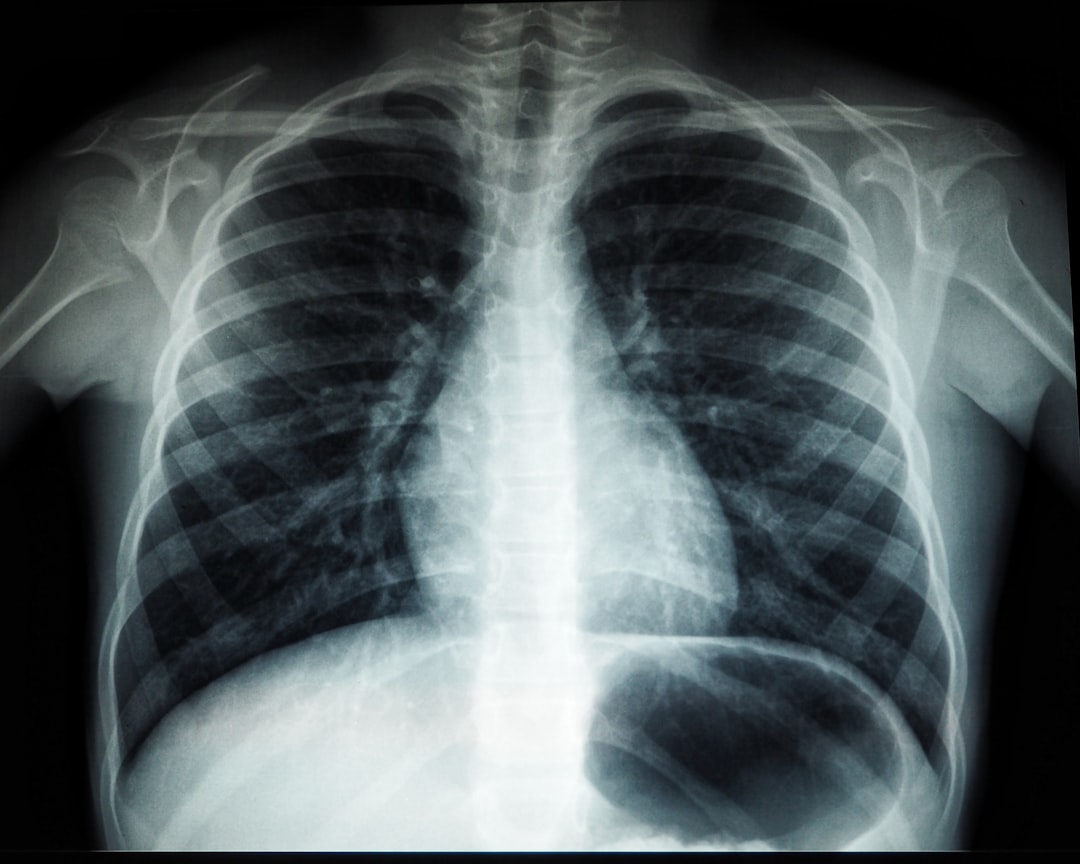

잠복결핵확인서란, 결핵균에 감염되었으나 현재 활성화된 결핵이 아닌 상태에서 발급되는 서류입니다. 이 서류는 주로 기관이나 학교, 직장에서 결핵 예방을 위한 검사의 일환으로 요청됩니다. 잠복결핵 확인서는 감염 여부에 대한 공식적인 증명서로 많은 곳에서 중요하게 다루어집니다. 특히 최근 들어 건강 관리의 중요성이 높아지는 가운데, 이 확인서는 매우 유용한 역할을 하고 있습니다.

잠복결핵확인서를 발급받기 위해서는 몇 가지 요건이 있습니다. 우선, 일반적으로 건강검진을 받아야 하며, 보통은 결핵 검사를 포함한 건강검진을 진행합니다. 이 검사에서 음성으로 확인되어야만 잠복결핵확인서를 발급받을 수 있습니다. 검사 종류로는 주로 튜베르쿨린 피부검사(TST)나 IGRA 혈액검사 등이 사용됩니다.